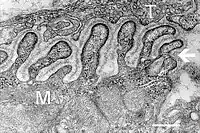

O terminal do neurônio motor se ramifica para encontrar uma ou mais fibras musculares. Perto delas, são formados os chamados botões sinápticos, os quais se encaixam em “dobras” do sarcolema. Essas dobras servem para aumentar a área de contato da membrana pós-sináptica com a pré-sináptica, o que influencia a eficiência da transmissão do sinal químico[2]. Os botões sinápticos do motoneurônio são envolvidos por células de Schwann, que formam uma capa sobre a junção neuromuscular. Essas células da glia são importantes para a formação, a manutenção e a regeneração das junções[3]. Tanto a membrana plasmática do motoneurônio quanto a das vesículas têm proteínas da família SNARE (do inglês, Soluble NSF Attachment Protein Receptor), complexos que catalisam a fusão entre as membranas vesicular e celular, a fim de haver liberação do conteúdo vesicular[4]. Cada botão sináptico tem as chamadas zonas ativas, regiões específicas de sua membrana plasmática com alta densidade eletrônica, que serve como um sinalizador para onde exatamente as vesículas sinápticas devem se fundir para liberar os neurotransmissores. As zonas ativas possuem canais de cálcio voltagem-dependentes, importantes para a liberação dos quanta de acetilcolina[2].

A placa motora é a região pós-sináptica, da membrana plasmática da fibra muscular. É o ponto específico onde há a conexão dessa célula com o motoneurônio. O sarcolema dessa região tem muitas dobras juncionais, como já mencionado, a fim de otimizar esse contato, canais nicotínicos, iônicos transmembrana, dependentes de ligante, no caso a acetilcolina, chamados de receptores de acetilcolina. Eles ficam nos ápices dessas dobras, formando aglomerados, enquanto canais de sódio voltagem-dependentes estão localizados mais profundamente nas dobras, e servem para mediar o início do potencial de ação da célula muscular[2]. O sarcoplasma na região da placa motora é rico em mitocôndrias, ribossomos e grânulos de glicogênio[5]. O sarcolema tem diversas proteínas que ajudam a conexão entre motoneurônio e fibra, como a NCAM (do inglês, Nerve Cell Adhesion Molecule), a agrina (proteoglicano que leva à diferenciação da região pós-sináptica e à formação dos aglomerados de receptores de acetilcolina; a fibra muscular tem receptores, chamados LRP4, para essa molécula), a quinase MuSK (Muscle Specific Kinase, um receptor tirosina quinase), a rapsina (proteína do sarcoplasma que age na conexão entre os receptores de acetilcolina e o citoesqueleto, no agrupamento desses receptores nas cristas das dobras juncionais)[3][6][7].